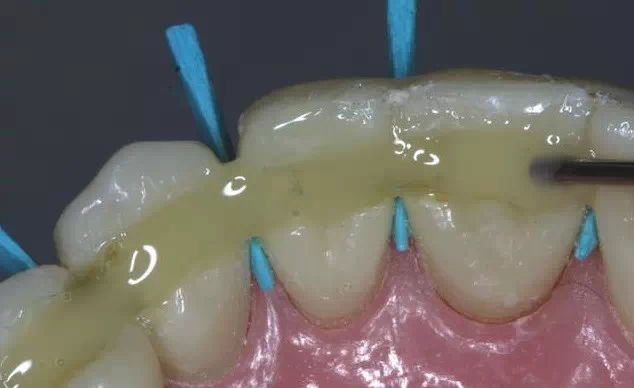

二、牙周系統(tǒng)治療

牙周炎發(fā)展到一定階段時,僅采用基礎治療難以取得較好療效,必須通過適時而合宜的手術治療挽救患牙,才能保持牙周組織健康,延長患牙在口腔內(nèi)的壽命,維持牙列的完整性,促進全身健康。其手段包括齦下刮治、根面平整、牙周翻瓣術、牙齦切除術、牙周夾板固定術等。